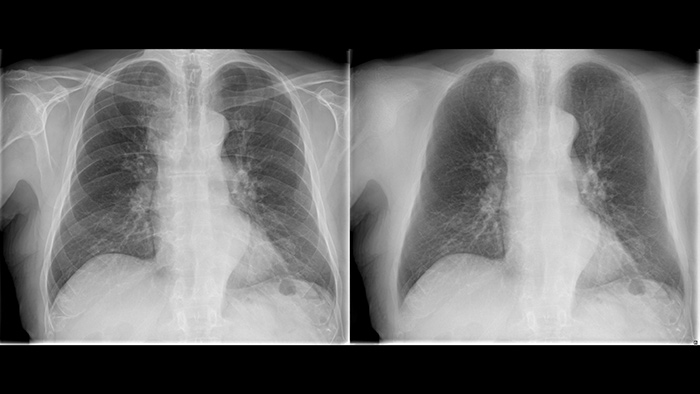

Improve your ability to provide confident diagnosis with two new image processing features

Philips UNIQUE 2 improves image quality with more homogeneous black backgrounds, reduced noise and automatic enhancement of small details

Philips Bone Suppression3 helps remove bone structures from chest images for an unobstructed view of soft tissue and can improve actionable nodule detection by up to 16.8% without the need to expose the patient to additional X-ray dose.4